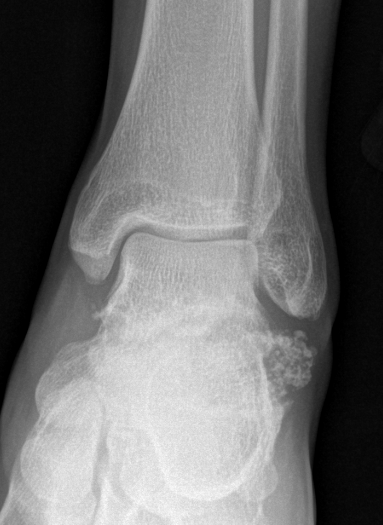

X-ray

Demonstrate calcified lesions / synovial osteochondromatosis

Synovial chondromatosis

Synovial osteochondromatosis

Ankle

Bojanic et al Foot Ankle Int 2021

- 17 patients

- 14/17 had anterior and posterior compartment involvement

- 2/17 dissatisfied

- no recurrence